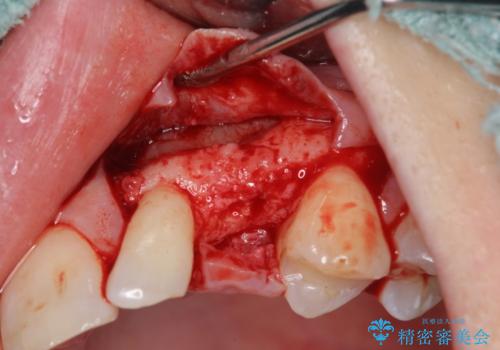

骨造成を伴う 前歯部インプラント治療

- 欠損している前歯のインプラント治療を希望され来院されました。

適切なインプラント埋入を行い、不足している骨量を補うため骨の造成を併用したインプラント治療を計画します。

前歯のインプラント治療は骨量・歯肉の厚み・インプラントの方向をしっかりと計画することで、審美的で長持ちを期待できるような仕上がりとなります。